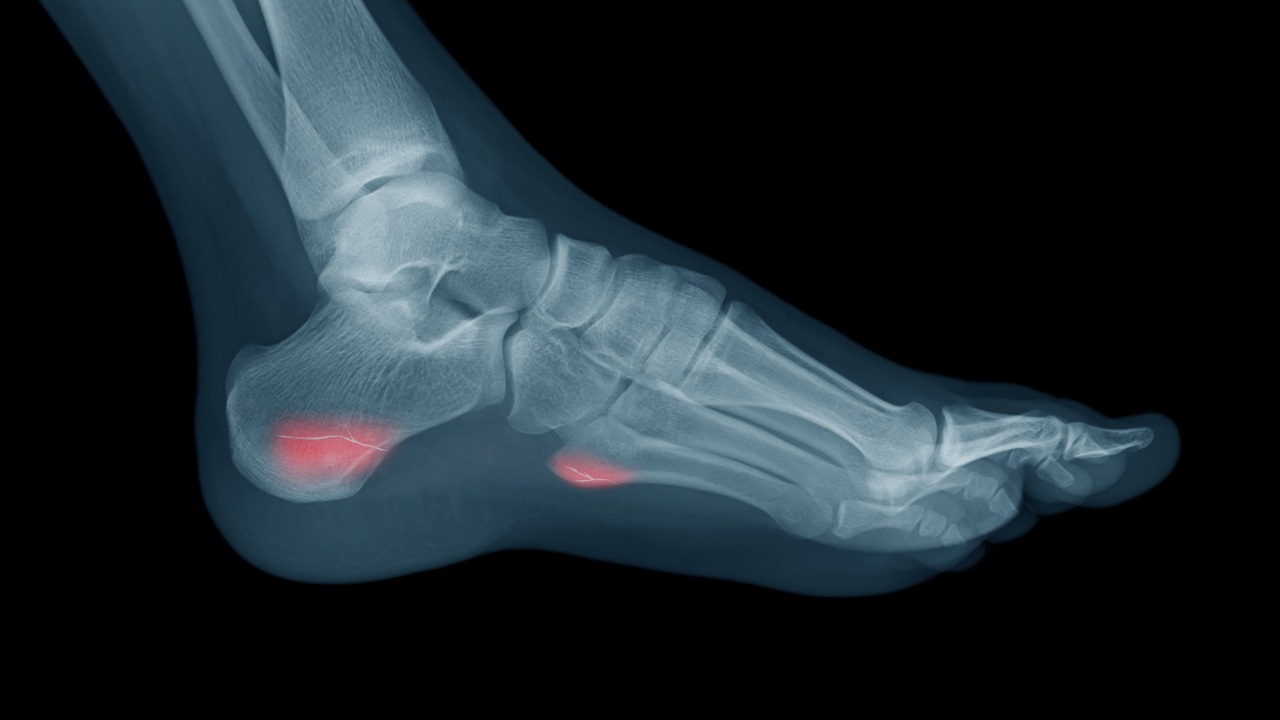

I did it pretty active about 10-12 months and still stretch achilles every day and usully do various exercises 5-6 times a week. The quality of life of 55 patients with calcaneal fractures treated by ORIF was compared 29 years after injury with that of 55 people from the standardised German population of the German-Health-Survey 1998 using the Short Form 36 SF-36 Wilcoxon test. Stress fractures of the calcaneus can occur from overuse or repeated high impact activities.

For good calcaneus fracture recovery one must take considerable care of the heel bone and not place any weight on it for approximately 10 weeks. Stress fractures of the calcaneus can be treated with noninvasive treatment. Most people heal from a calcaneal stress fracture within a few months.

SymptomsSome calcaneal fractures are obvious resulting in an inability to put weight on the heel swelling of the heel and bruising of the heel and anklePain is usually severe enough to require an emergency room visit. Most often patients will have to be on crutches and may even require a brief period of cast immobilization to allow the fracture to heal. They are the second most common stress fracture of the foot after navicular stress fractures.

This is called Mondor sign and is a strong indicator for calcaneus fracture. For good calcaneus fracture recovery one must take considerable care of the heel bone and not place any weight on it for approximately 10 weeks after surgery. If the fracture is caused by a stress fracture over time then symptoms may be far more vague.